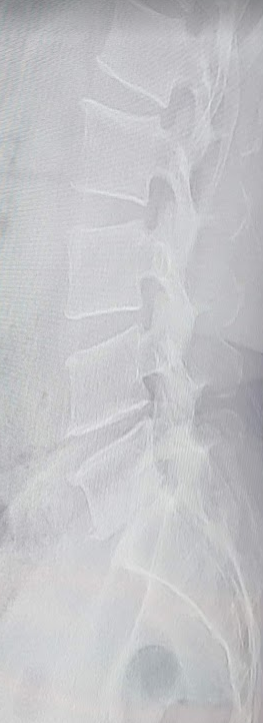

병원에 가서 받은 결론은 4,5번 경증 디스크 증상.

그래도 나머지 척추들은 상태가 좋다는 말씀을 해주셨고, 오늘 3번째로 진료를 받을 때 선생님이 엑스레이 사진을 한참 보시더니 뼈가 멍 들었다. 라는 말씀을 하십니다.

디스크가 멍드는 질환의 정확한 명칭은 '디스크내장증'